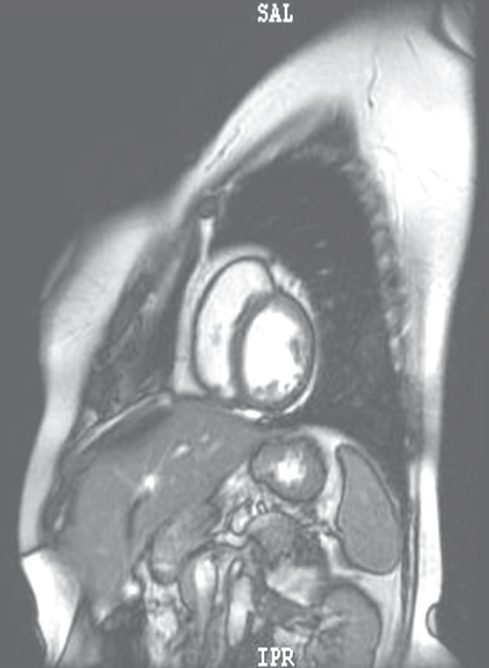

摘要:關(guān)于擴(kuò)張性心肌病的最新治療,小巷深處的隱藏寶藏正逐漸為人們所發(fā)現(xiàn)。通過(guò)先進(jìn)的醫(yī)療技術(shù)和方法,擴(kuò)張性心肌病的治療取得了新的進(jìn)展。這些治療方法旨在改善心臟功能,提高患者生活質(zhì)量。小巷深處的醫(yī)療機(jī)構(gòu)或?qū)<铱赡茈[藏著寶貴的治療經(jīng)驗(yàn)和方法,為尋求最佳治療方案的病患帶來(lái)希望。更多詳細(xì)信息需要進(jìn)一步探索和研究。

擴(kuò)張性心肌病是一種嚴(yán)重的心臟疾病,但“心之港灣”為你帶來(lái)希望,這里的專家團(tuán)隊(duì)一直在深入研究擴(kuò)張性心肌病的最新治療方法,并深知每位患者都渴望得到最佳的治療和關(guān)懷,他們努力不懈,為患者帶來(lái)生機(jī)和新生。